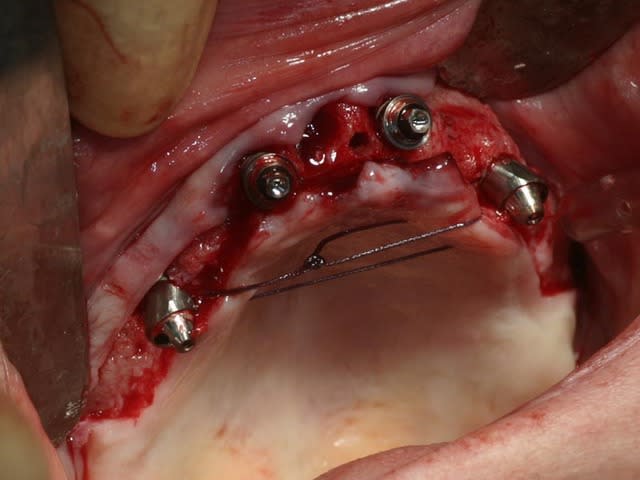

bon, toujours aussi speed je suis, mais après certaines réclamations, et malgrès ma réticence à poser un cas non "consolidé", voici en avant première mon premier all on 4, version photos ratées et non retouchées, mais... speed je suis je vous disais ;)

sto le bla bla, et pasons le diaporama... bon voyage au pays de la mise en charge immédiate totale au maxillaire de fille carole sur dame ginette, une patiente en or que j' adore, et pour qui je suis très très heureuse d' avoir pu réaliser cette chirurgie et la première étape prothétique.....

Tu as vraiment bien réussi à longer le plancher sinusal et apparemment la patiente pourra se pendre aux implants...

Tu as utilisé des Nobel Speedy si je ne me trompe pas.

Tu as eu un couple final de 50N au maxillaire ? Si c'est le cas, bravo.

Peux tu nous en dire un peu plus sur les implants, leurs diamétres et leur longueurs ?

du 4 par 15 ?